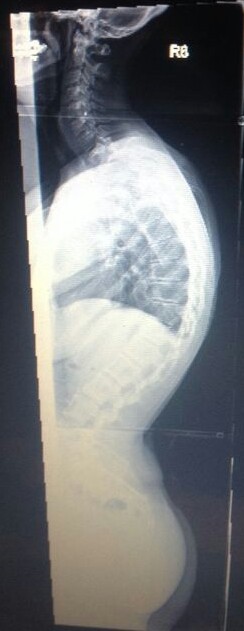

Diagnose: thorakale Kyphose 80 Grad

Meine Name ist Claudia bin 30 Jahre und habe eine Hyperkyphose von 80 Grad die im November 2013 endlich festgestellt wurde, eine leichte Skoliose hatte ich schon von Kind an . Am Ende war es so das ich seit über 20 Jahren mit Schmerzen lebe , bis mir vor 4 Jahren wegen unerträglichen Schmerzen eine Bandscheiben OP gemacht wurde da es angeblich davon kam!!! ( nur leider lagen diese ganzen Ärzte bei ( ca.20 Ärzte von Orthopäden, Neurologen und so weiter ) denen ich im lauf der 20 jahre war alle falsch , alle meinten das wären die Bandscheiben :(

Seit November 2013 bin ich im BGU Frankfurt am Main daher auch die Diagnose wegen einer 2. Meinung war ich auch noch in Würzburg, diese kamen auf das gleiche . Irgendwie froh bin ich schon das ich nun endlich weiss was ich habe und wie es zu behandeln ist .

Im Anhang 2 Bilder von mir

IMG-20131213-WA0004~2.jpg

IMG-20131213-WA0004~2.jpg (28.61 KiB) 6612 mal betrachtet